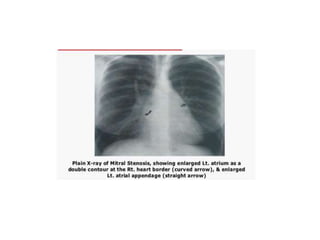

• Chest X ray features of MS

• Mitralisation of heart - Straightening of left heart border d/t small

aortic knuckle, dilated pulmonary artery and prominent left atrial

appendage.

• Double contour of right heart border (shadow within shadow) - LA

enlargement.

• Evidence of pulmonary hypertension - Dilated pulmonary arteries at

hilum with peripheral pruning.

• Elevation of left upper lobe bronchus and splaying of carina - LA

• Kerley Blines - dense,short, horizontal lines in costophrenic region

when pulmonary venous pressure is between 20-30mmHg.

• Kerley A lines - Straight,dense lines running towards hilum when

pulmonary venous pressure is >30mmHg.

• Upturned apex - inverted moustache sign

• Chest Xray features of MS

• Mitralisation ofheart - Straightening of left heart border d/t small aortic knuckle, dilated pulmonary artery and prominent left atrial appendage. • Double contour of right heart border (shadow within shadow) - LA enlargement. • Evidence of pulmonary hypertension - Dilated pulmonary arteries at hilum with peripheral pruning. • Elevation of left upper lobe bronchus and splaying of carina - LA enlargement. • Kerley Blines - dense,short, horizontal lines in costophrenic region when pulmonary venous pressure is between 20-30mmHg. • Kerley A lines - Straight,dense lines running towards hilum when pulmonary venous pressure is >30mmHg. • Upturned apex - inverted moustache sign